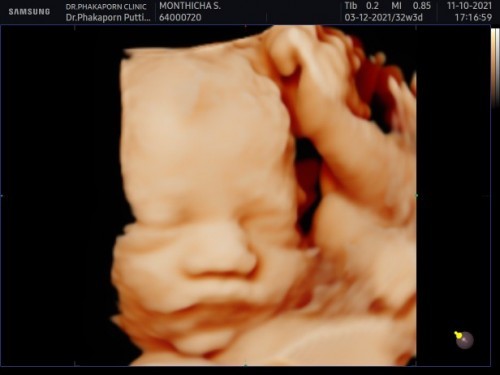

กำหนด 3 ธันวาคมนี้แล้วจ้าาา

Post reply image